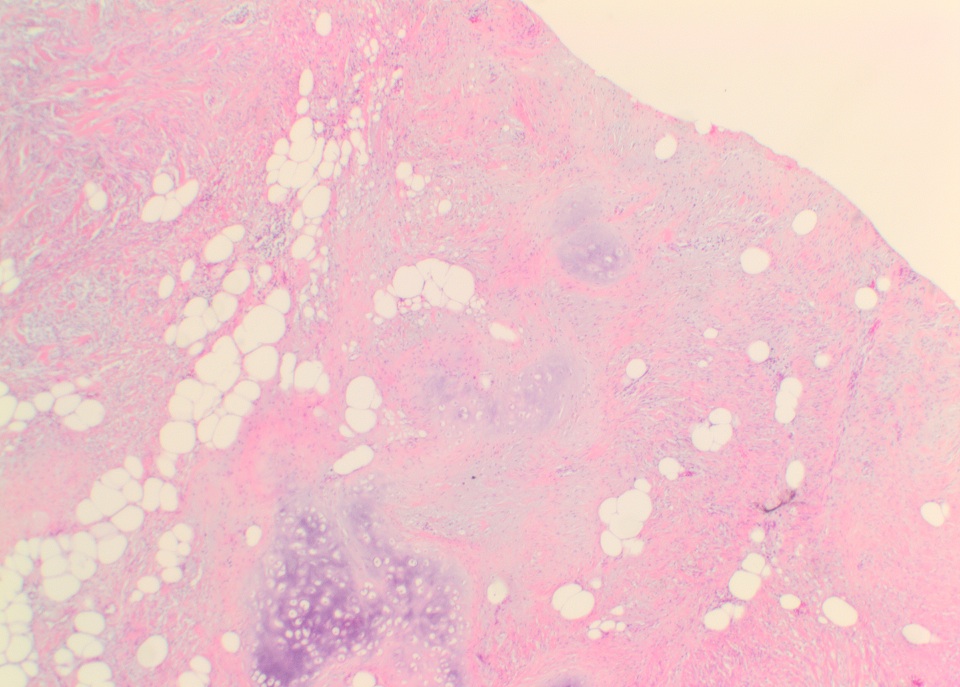

Micro images:

The conventional histologic appearance is of bland fibroblast-like spindle cells with relatively short, stubby nuclei. The cells are interspersed between collagen bundles and a variable amount of adipose tissue. The stroma can show hyalinization and / or myxoid change. Mast cells may be conspicuous (Goldblum: Enzinger and Weiss's Soft Tissue Tumors, 6th ed, 2013, Am J Surg Pathol 2016;40:361). Several different variants of MTMF have been described: cellular, infiltrating, collagenized / fibrous, lipomatous, myxoid, epithelioid and deciduoid-like. Areas of smooth muscle, bone and cartilage can be seen (Am J Surg Pathol 2009;33:1085). Rare tumors may show a neurilemmoma-like pattern. "Symplastic" or degenerative cytologic atypia - enlarged, hyperchromatic, multinucleated cells - can be present (Am J Surg Pathol 2016;40:361).

Micro images:

The conventional histologic appearance is of bland fibroblast-like spindle cells with relatively short, stubby nuclei. The cells are interspersed between collagen bundles and a variable amount of adipose tissue. The stroma can show hyalinization and / or myxoid change. Mast cells may be conspicuous (Goldblum: Enzinger and Weiss's Soft Tissue Tumors, 6th ed, 2013, Am J Surg Pathol 2016;40:361). Several different variants of MTMF have been described: cellular, infiltrating, collagenized / fibrous, lipomatous, myxoid, epithelioid and deciduoid-like. Areas of smooth muscle, bone and cartilage can be seen (Am J Surg Pathol 2009;33:1085). Rare tumors may show a neurilemmoma-like pattern. "Symplastic" or degenerative cytologic atypia - enlarged, hyperchromatic, multinucleated cells - can be present (Am J Surg Pathol 2016;40:361).